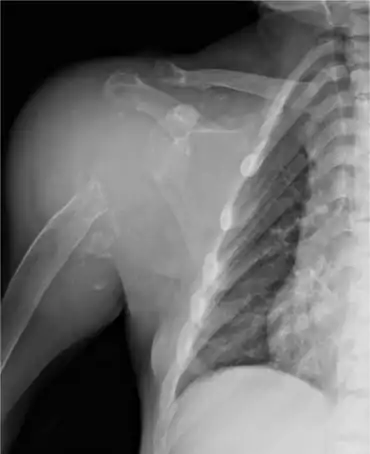

Anteroposterior shoulder radiography of individual on renal replacement treatment